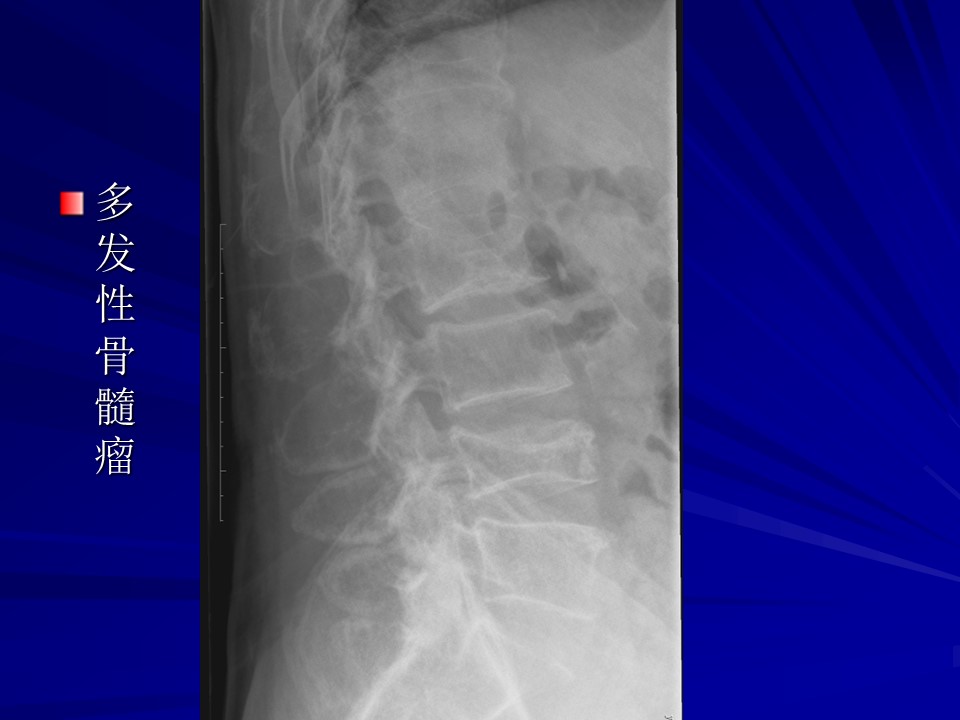

“常见骨肿瘤的X线诊断” 的相关文章